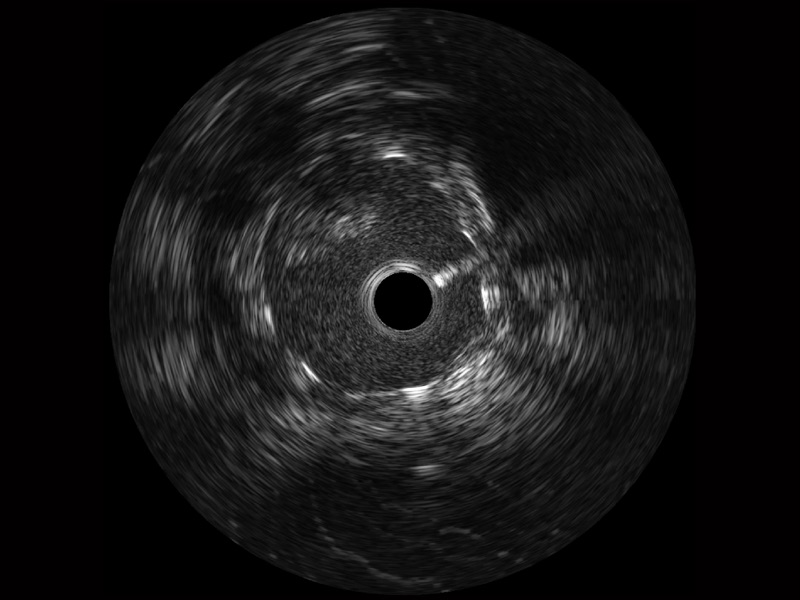

• 诸侯快讯官网宽频IVUS图像

• 传统IVUS图像

对比传统IVUS导管成像,诸侯快讯官网宽频IVUS图像的近场支架梁显影更细腻,远场中膜外血管仍清晰可辨,兼顾远中近,兼顾分辨力与穿透深度